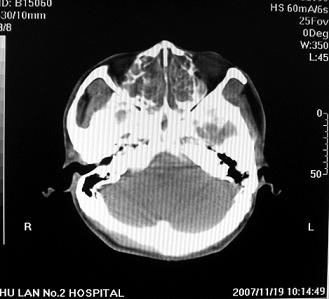

标题: CT10521:男。32岁,副鼻窦ct,请会诊。 [打印本页]

标题: CT10521:男。32岁,副鼻窦ct,请会诊。

男。32岁,鼻塞,流涕一年余。

考虑鼻腔内翻性乳头状瘤,筛窦、上颌窦炎症。建议进一步检查。

炎性病变.息肉阻塞副鼻窦口导致窦腔内潴留.

软组织密度影填满上颌蚪 筛窦及鼻腔,并导致筛骨 上颌窦内侧壁明显骨质破坏。多考虑:内翻性乳头状瘤!

双侧鼻腔内低密度软组织影,骨壁无明显破坏,鼻腔无扩大,双侧上颌窦、筛窦软组织影,窦壁增厚,结合临床考虑鼻息肉合并慢性上颌窦炎。